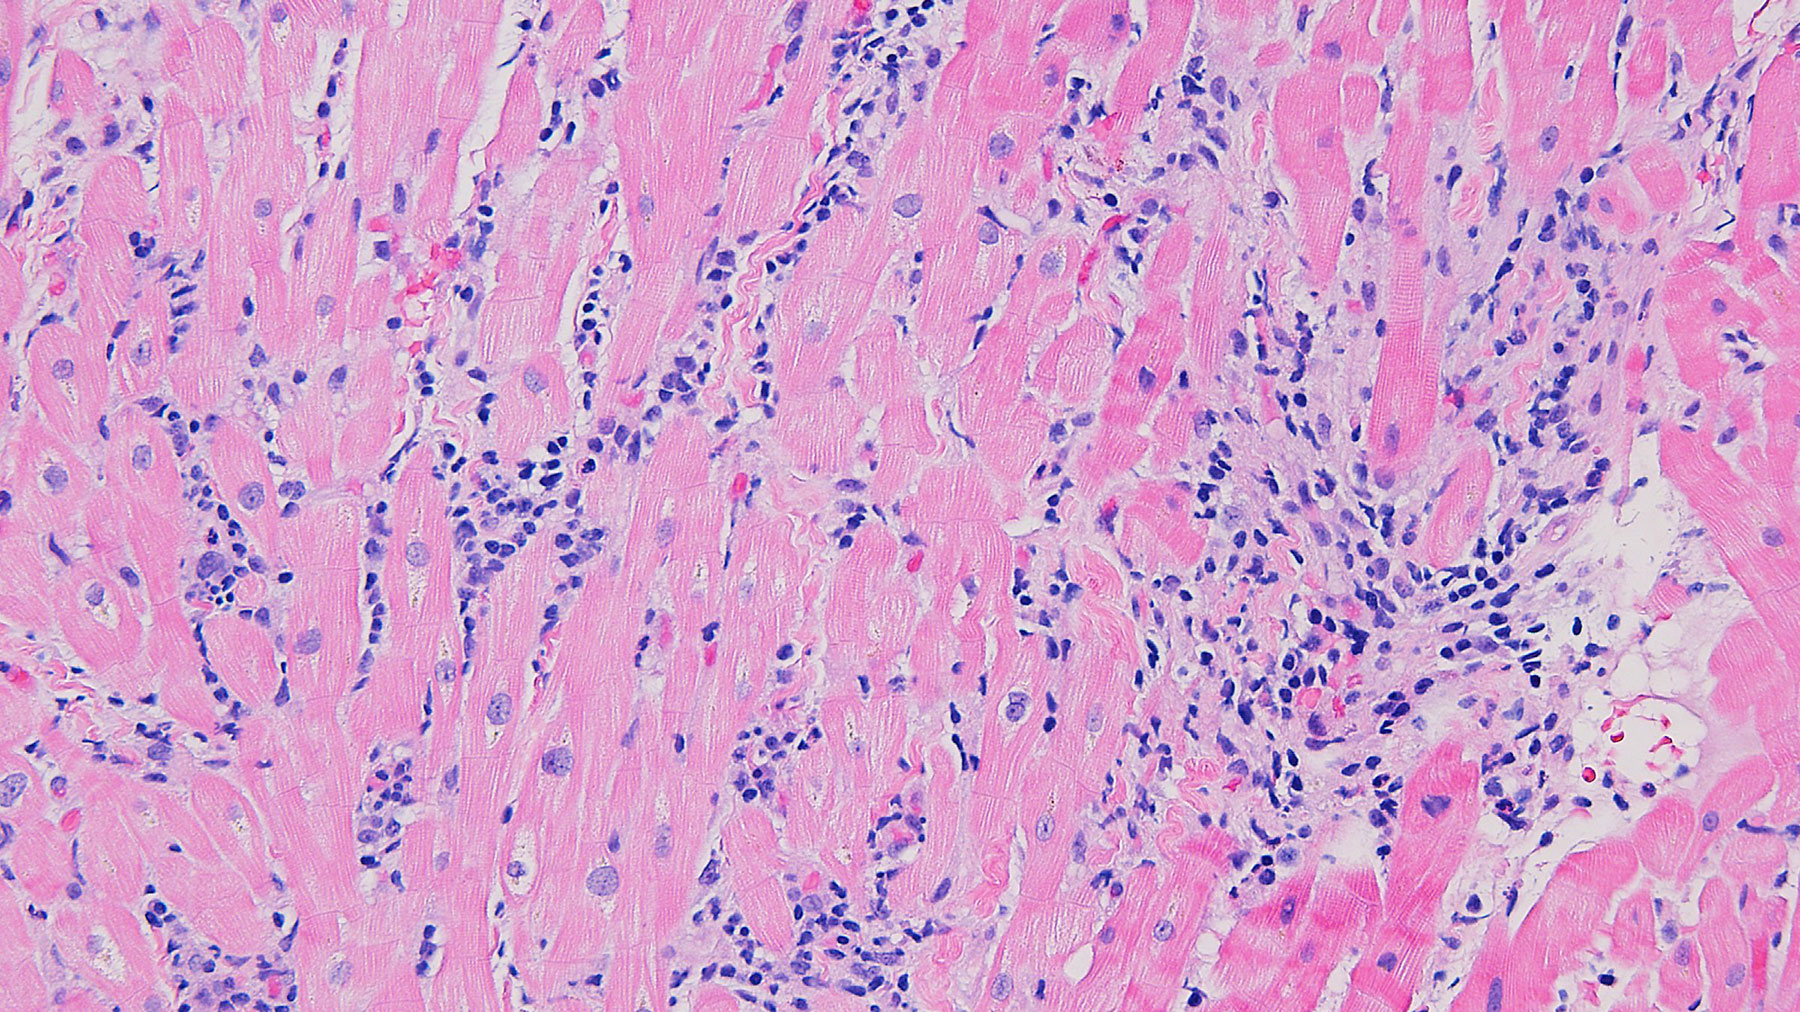

Figure D. Trichrome stain x20

Histology: Biopsy of the myocardial tissue performed at one month after the transplant showed myocardial tissue with diffuse and severe polymorphous mononuclear infiltrates with extensive myocyte damage, interstitial edema, vasculitis and focal necrosis (H&E staining in Figures A, C & E, and corresponding trichrome stains in Figures B, D & F). Special immunohistochemistry (IHC) stain for CD4 in a consecutive section from E and F (Figure G) shows a predominant infiltrate for helper cells.  All these features are consistent with severe acute cellular rejection, ISHLT 2004 Grade 3R (ISHLT 1990 Grade 3B).